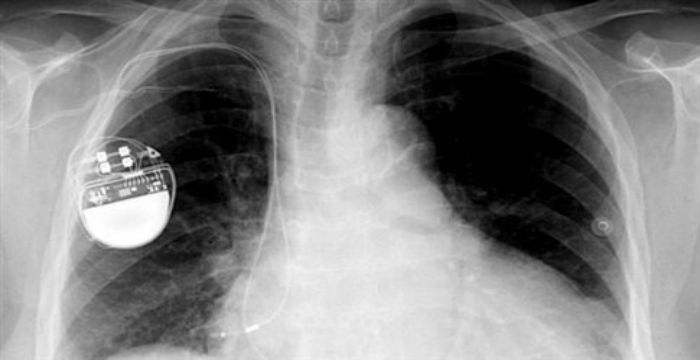

Ο πρώην αντιπρόεδρος των ΗΠΑ Ντικ Τσένι ζήτησε από τους γιατρούς του να απενεργοποιήσουν τη λειτουργία ασύρματης δικτύωσης στον βηματοδότη που επρόκειτο να του εμφυτεύσουν.

Όπως επισημαίνει τώρα ο δικτυακός τόπος του περιοδικού Science, ειδικοί σε θέματα ασφάλειας υπολογιστών έχουν αποδείξει εδώ και καιρό ότι είναι δυνατό να παρέμβει κανείς σε εμφυτεύσιμες συσκευές όπως οι βηματοδότες, οι απινιδωτές και οι αντλίες ινσουλίνης.

Πολλά από τα σύγχρονα μοντέλα μπορούν να ρυθμιστούν αν χρειαστεί μέσω ενός φορητού ελεγκτή που συνδέεται με τη συσκευή μέσω Bluetooth. Υπάρχουν όμως και συσκευές που συνδέονται απευθείας στο Διαδίκτυο μέσω WiFi, και είναι δυνητικά πιο ευπαθείς σε επιθέσεις.